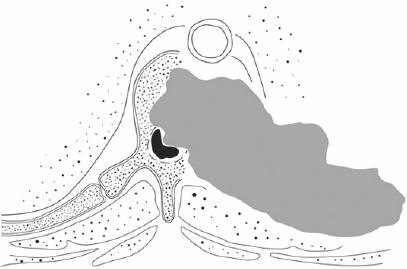

Cancer of the Spine

Cancer of the spine, both secondary and primary, are of particular interest to this practice. Dr Mobbs has undertaken further training in complex spine cancer surgery and reconstruction.

Click on the thumbnails for enlarged view